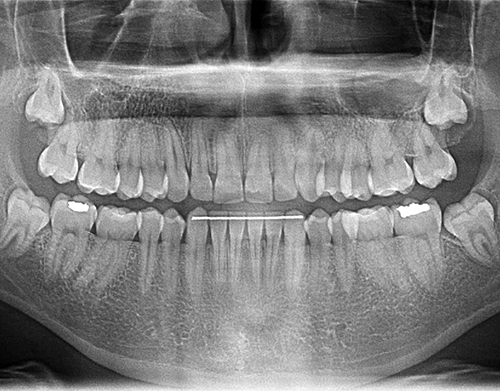

ORAL DİAGNOZ VE RADYOLOJİ İŞLEMLERİ

Teşhis ve tedavi planlamasının yapıldığı, hastalarımızı ilk olarak karşıladığımız bölümümüzdür. Kurumumuza gelen hastalarımız şikayetleri doğrultusunda tedavilerine başlamadan önce uzman diş hekimleri tarafından muayene edilirler. Eğer gerek görülürse radyolojik görüntüleri alınır.

Kurumumuzda teşhis için gerekli en ileri teknoloji kullanılarak hastalarımızın radyografik değerlendirmeleri yapılır. Bu değerlendirmeler sonucu hastalarımızın tedavi planları oluşturulur.